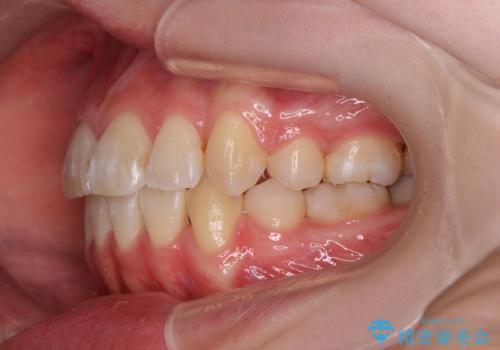

綺麗な歯並びを手に入れられたと同時に、口元もスッキリし、仕上がりに満足いただくことができました。

突き出た前歯を治したい 小臼歯抜歯+マルチブラケット矯正